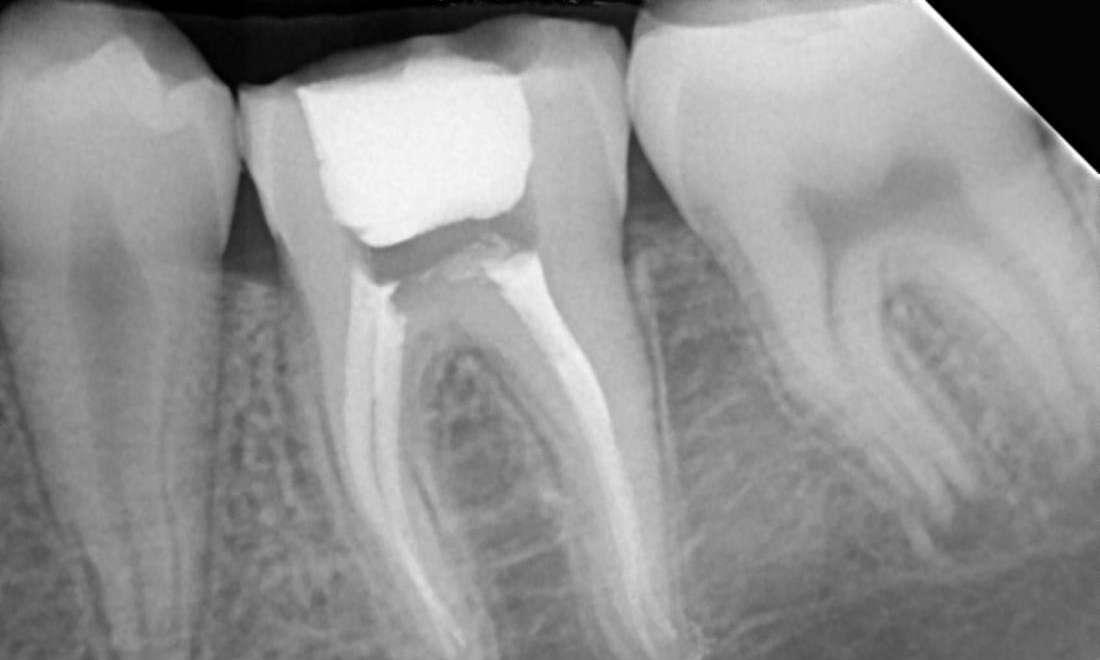

Root Canal Treatment - Lower Molar

These are photographs of Dr. Dennis Anithottam's patient/treatment . Photographs are for informational purposes only because individual treatment results will vary from patient to patient. Some patients may not be candidates for treatment.” This is directly referenced from the ADA & C compliance codes.